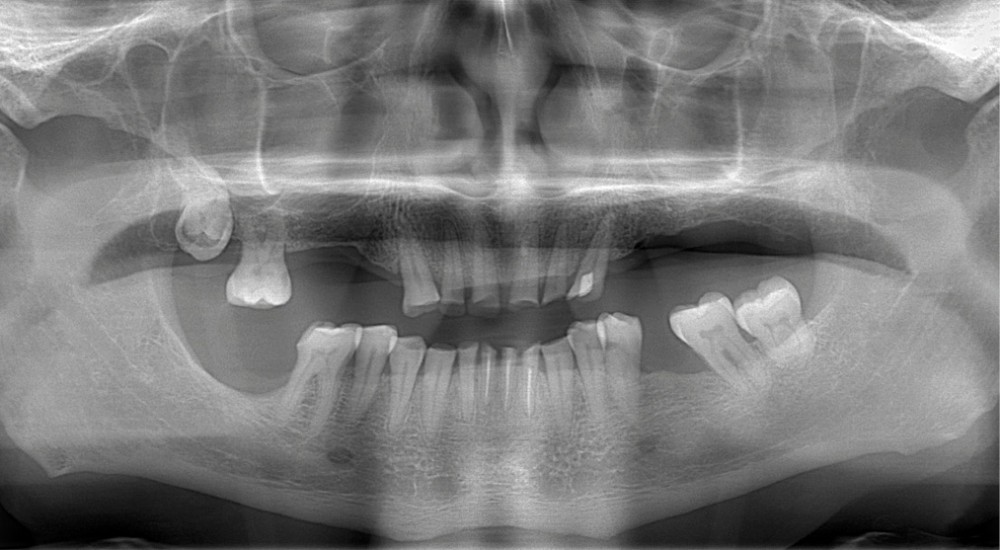

Un patient de 68 ans arrive au cabinet ; il présente de nombreux édentements ainsi qu’une usure parafonctionnelle très avancée.

• L’examen intrabuccal montre de nombreux édentements non compensés (14, 15, 16, 24, 25, 26, 27, 47 et 36) ainsi que des pertes de substance très importantes, notamment dans le secteur antérieur.

La perte de dimension verticale par usure prématurée nécessite d’augmenter cette dernière de façon importante, et en une seule fois.

À cet effet, il est proposé au patient de réaliser précocement la pose d’implants postérieurs simultanément à des soulevés de sinus bilatéraux, afin d’éviter la prothèse amovible, même transitoire.